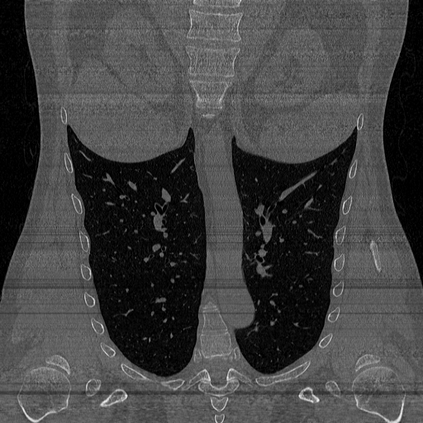

CT reconstruction provides radiologists with images for diagnosis and treatment, yet current deep learning methods are typically limited to specific anatomies and datasets, hindering generalization ability to unseen anatomies and lesions. To address this, we introduce the Multi-Organ medical image REconstruction (MORE) dataset, comprising CT scans across 9 diverse anatomies with 15 lesion types. This dataset serves two key purposes: (1) enabling robust training of deep learning models on extensive, heterogeneous data, and (2) facilitating rigorous evaluation of model generalization for CT reconstruction. We further establish a strong baseline solution that outperforms prior approaches under these challenging conditions. Our results demonstrate that: (1) a comprehensive dataset helps improve the generalization capability of models, and (2) optimization-based methods offer enhanced robustness for unseen anatomies. The MORE dataset is freely accessible under CC-BY-NC 4.0 at our project page https://more-med.github.io/